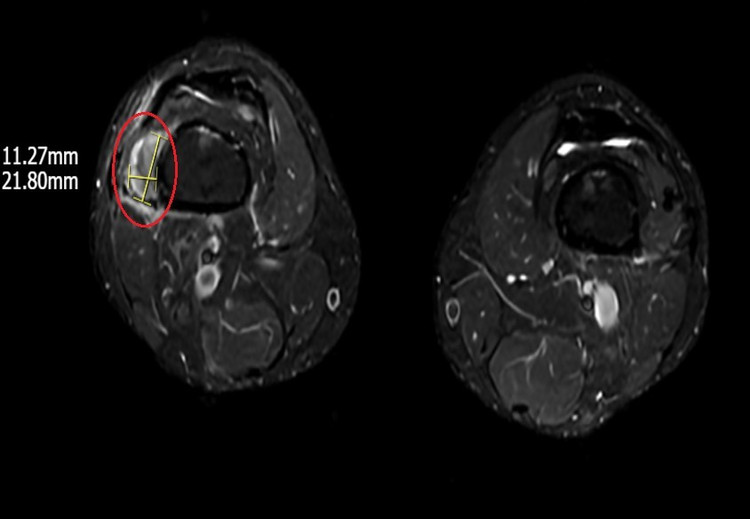

Hình ảnh khối u vùng vị trí phần mềm dưới đùi phải trên phim MRI - Ảnh BVCC

“Việc cần làm là phải xác định được vị trí của khối u để loại bỏ triệt để căn nguyên gây thiếu hụt phốt pho khiến xương giòn yếu. Tuy nhiên, thách thức của quá trình chẩn đoán là u tăng tiết FGF23 thường là u lành tính, nhỏ, không sưng đau và có thể ở xuất hiện ở bất kỳ vị trí nào trên cơ thể.

Để củng cố chẩn đoán bệnh cần phải định lượng chỉ số FGF23 trong máu, tuy nhiên, ở Việt Nam hiện chưa có xét nghiệm này. Do đó, chúng tôi chỉ định bệnh nhân chụp PET/CT toàn thân với chất phóng xạ kết hợp chụp MRI, siêu âm, cuối cùng tìm thấy 1 khối u kích thước 1-2 cm vị trí phần mềm dưới đùi phải”, ThS.BSNT Vân chia sẻ.